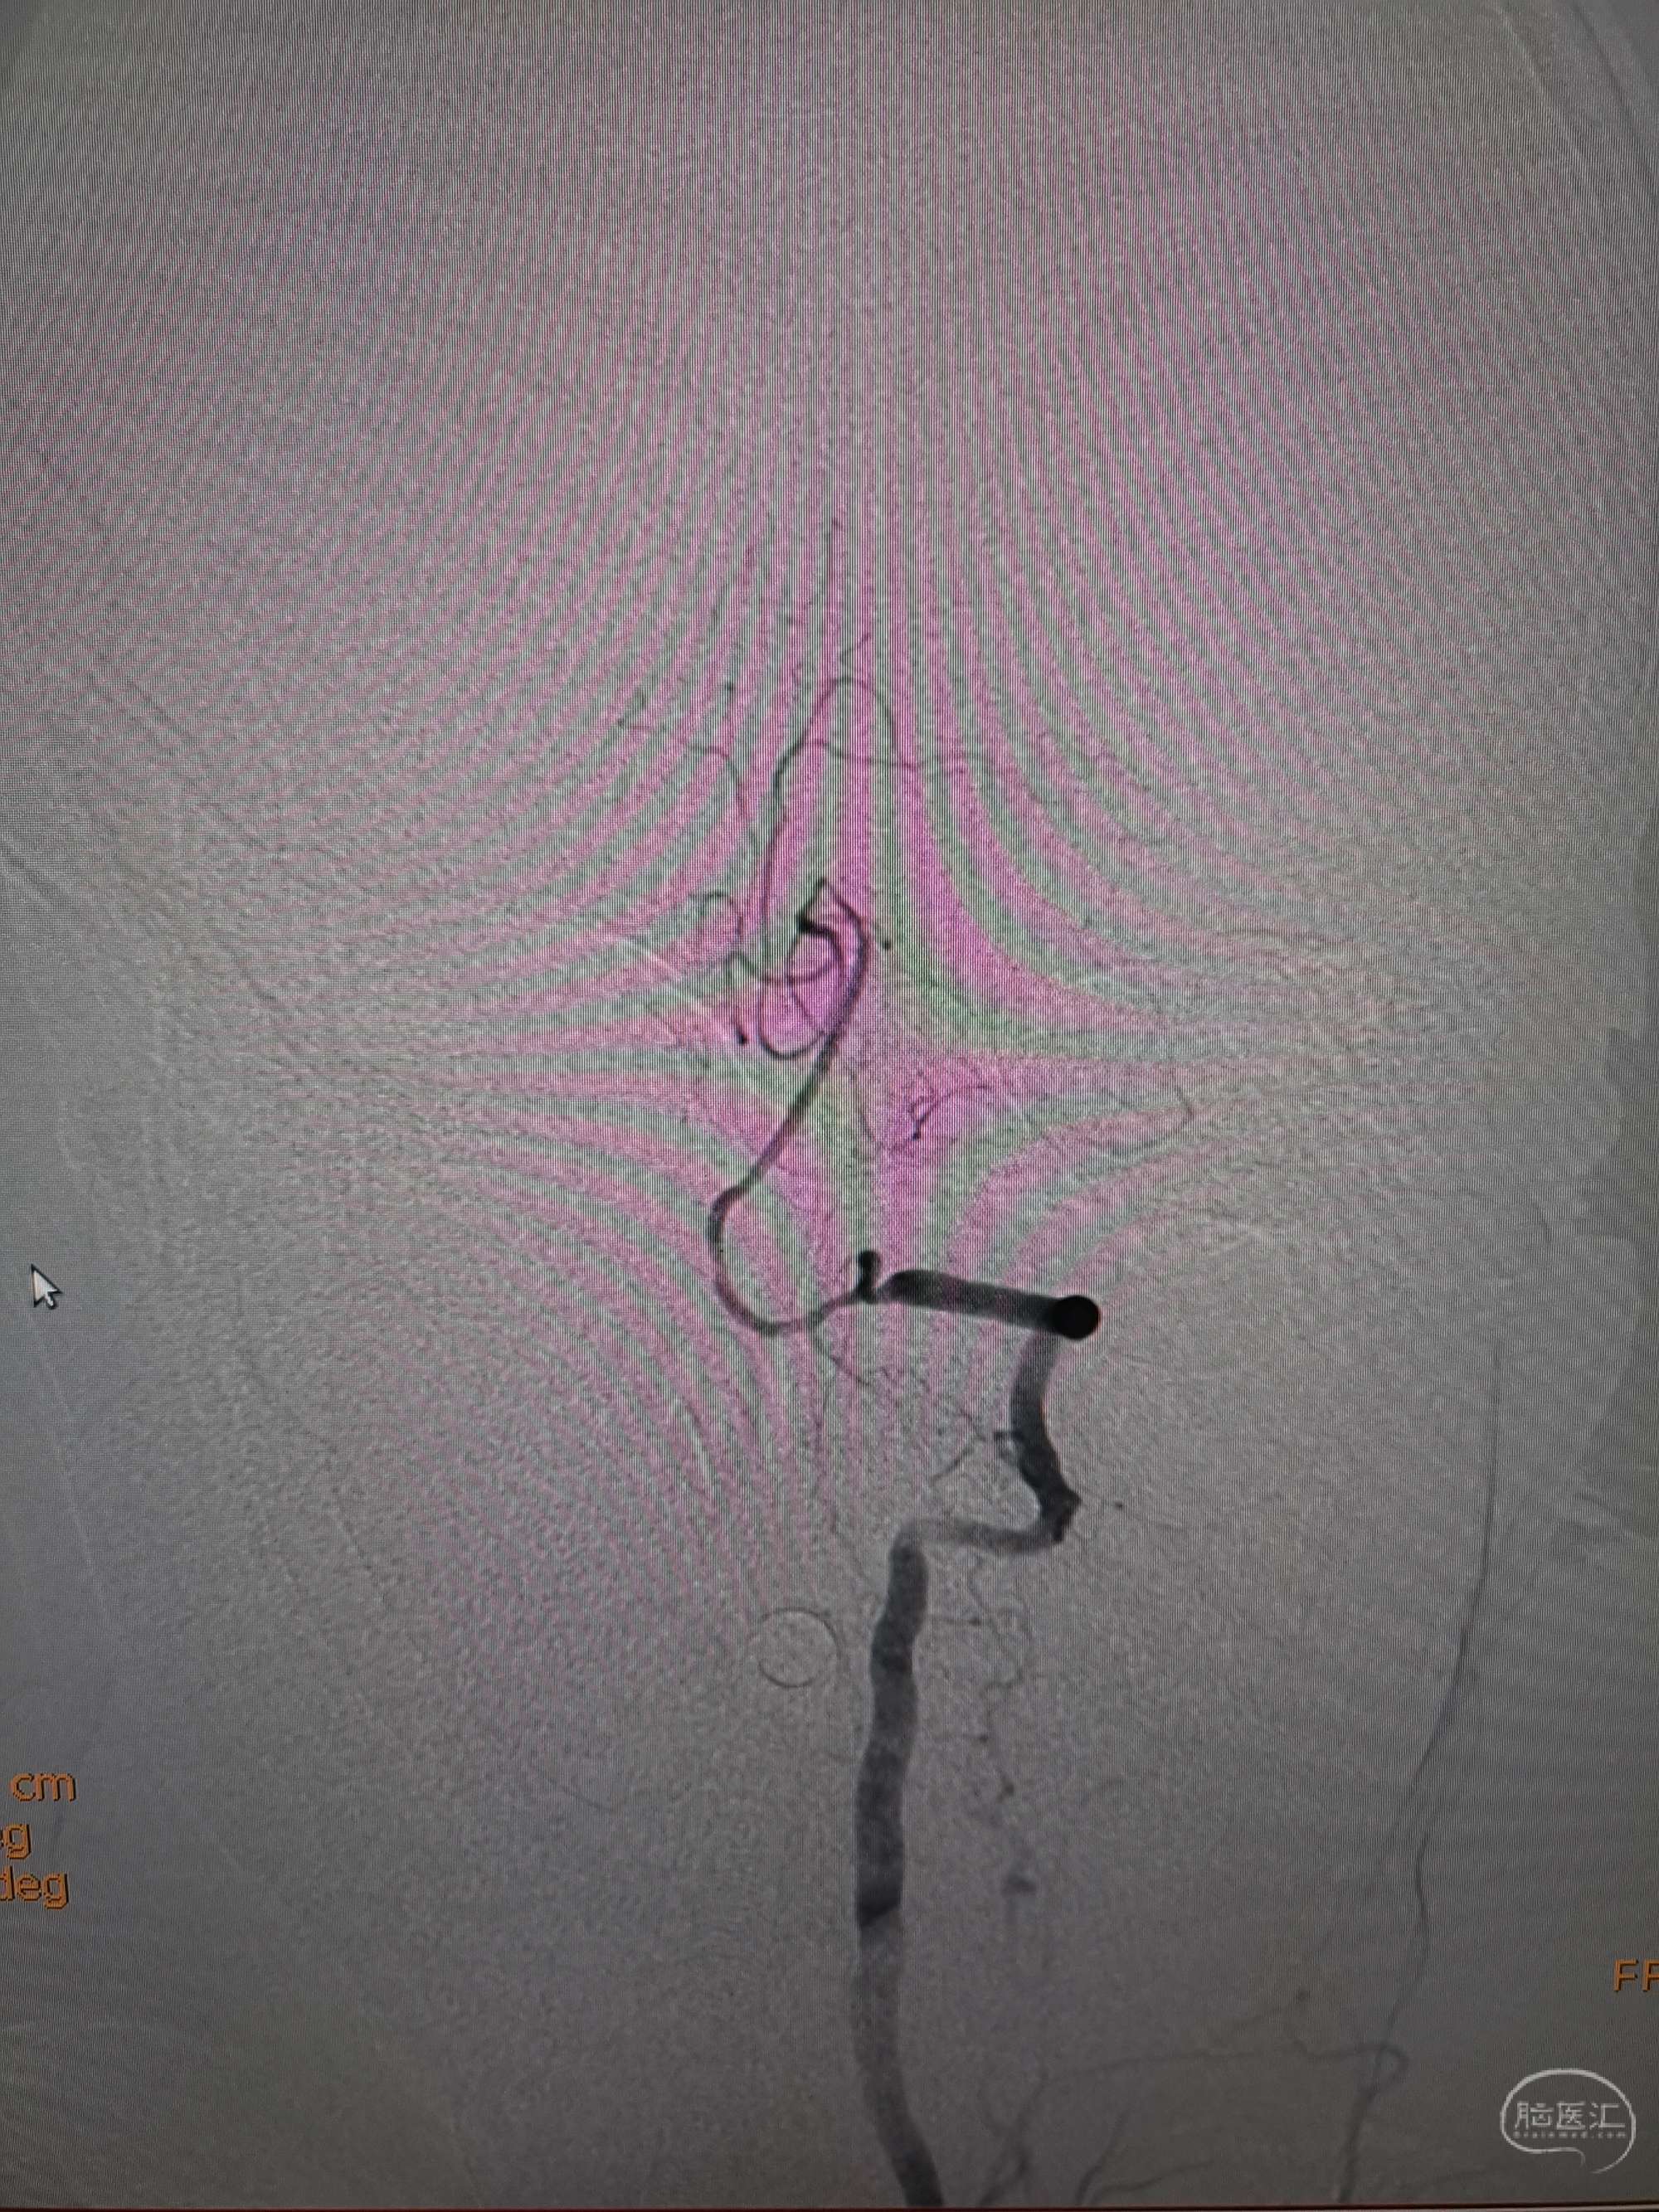

手术过程

在微导管支撑下先将微导丝和微导管穿过闭塞段,微导管超选造影证实位于基底动脉真腔后更换300cm外周交换导丝,撤出微导管后按从小到大,从远到近的原则行球囊扩张,本例手术选择了1.5✖️15、2.0✖️20、2.5✖️20球囊进行扩张,扩张满意后植入Enterprise支架,手术结束。

术后造影见左侧椎动脉闭塞段管腔恢复正常直径,远端血运良好。